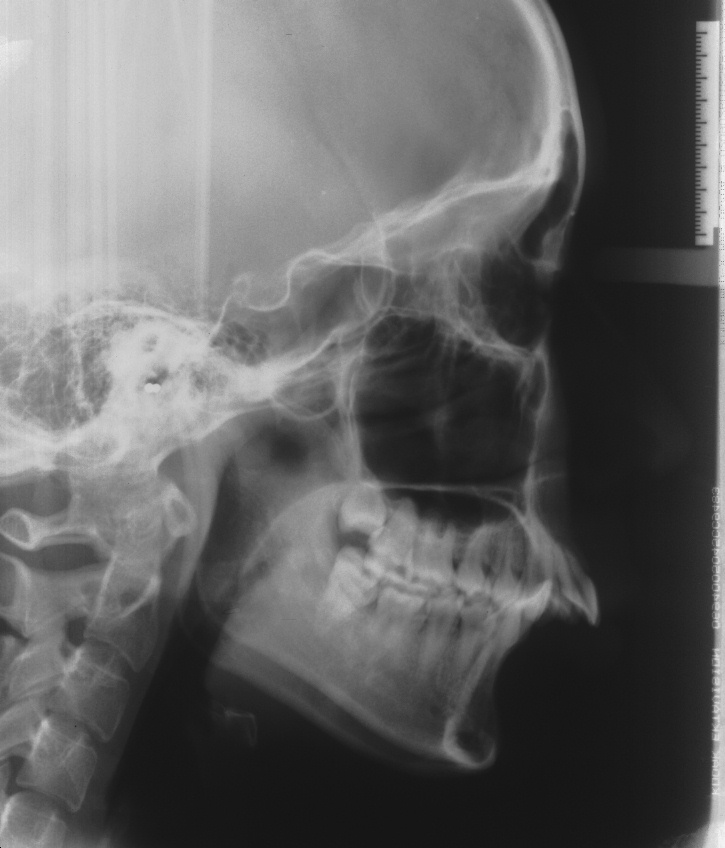

치료 전 사진입니다.